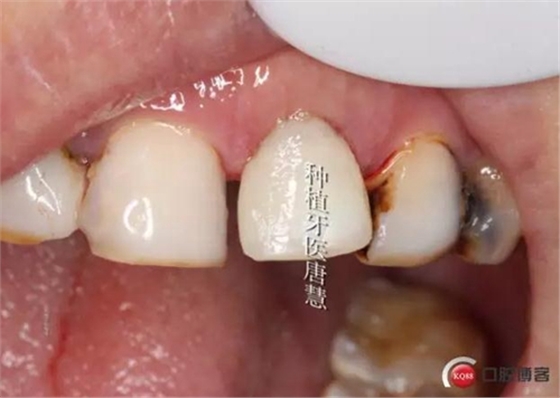

制作個(gè)性化臨時(shí)基臺(tái)

完成臨時(shí)修復(fù)